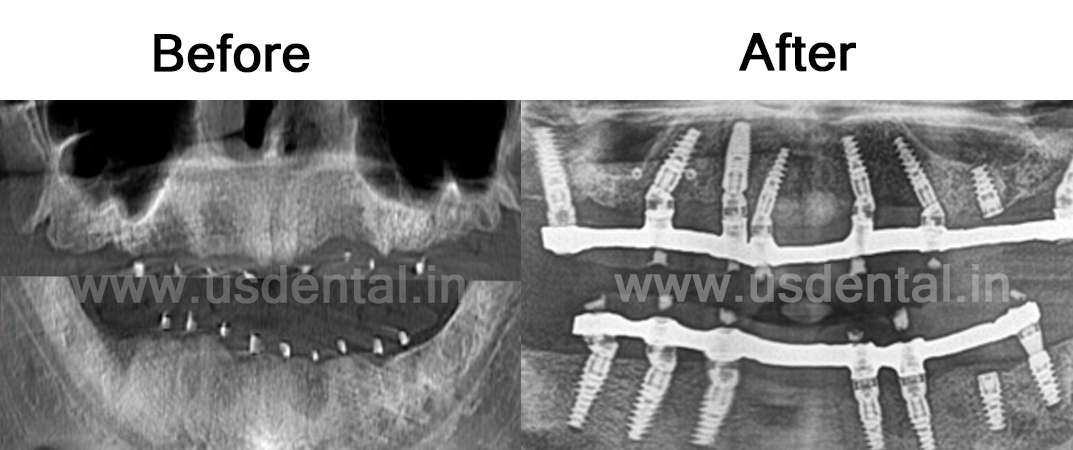

Case of the Month – Full Mouth Rehabilitation with Implants

A patient visited the US Dental Clinic with the concern of missing teeth in both the upper and lower jaws. He had been using loose-fitting removable dentures and expressed the desire for a more stable and permanent solution with fixed teeth.

Upon clinical examination, it was found that all teeth were missing. However, the oral ridges appeared to be in good condition. To further evaluate bone quality and quantity for implant placement, the patient was advised to undergo a CBCT scan of both jaws.

The CBCT reports were thoroughly reviewed by our implantologist. The scans revealed adequate bone height and width, making the patient clinically eligible for full-mouth dental implants. The patient was scheduled for implant surgery. A total of 8 implants were placed in the upper jaw and 7 implants in the lower jaw, all with good primary stability and torque. Following successful implant placement, impressions were taken and sent to the dental lab for fabrication of the final prosthesis. A hybrid denture prosthesis was delivered, providing the patient with a stable, functional, and natural-looking set of fixed teeth.